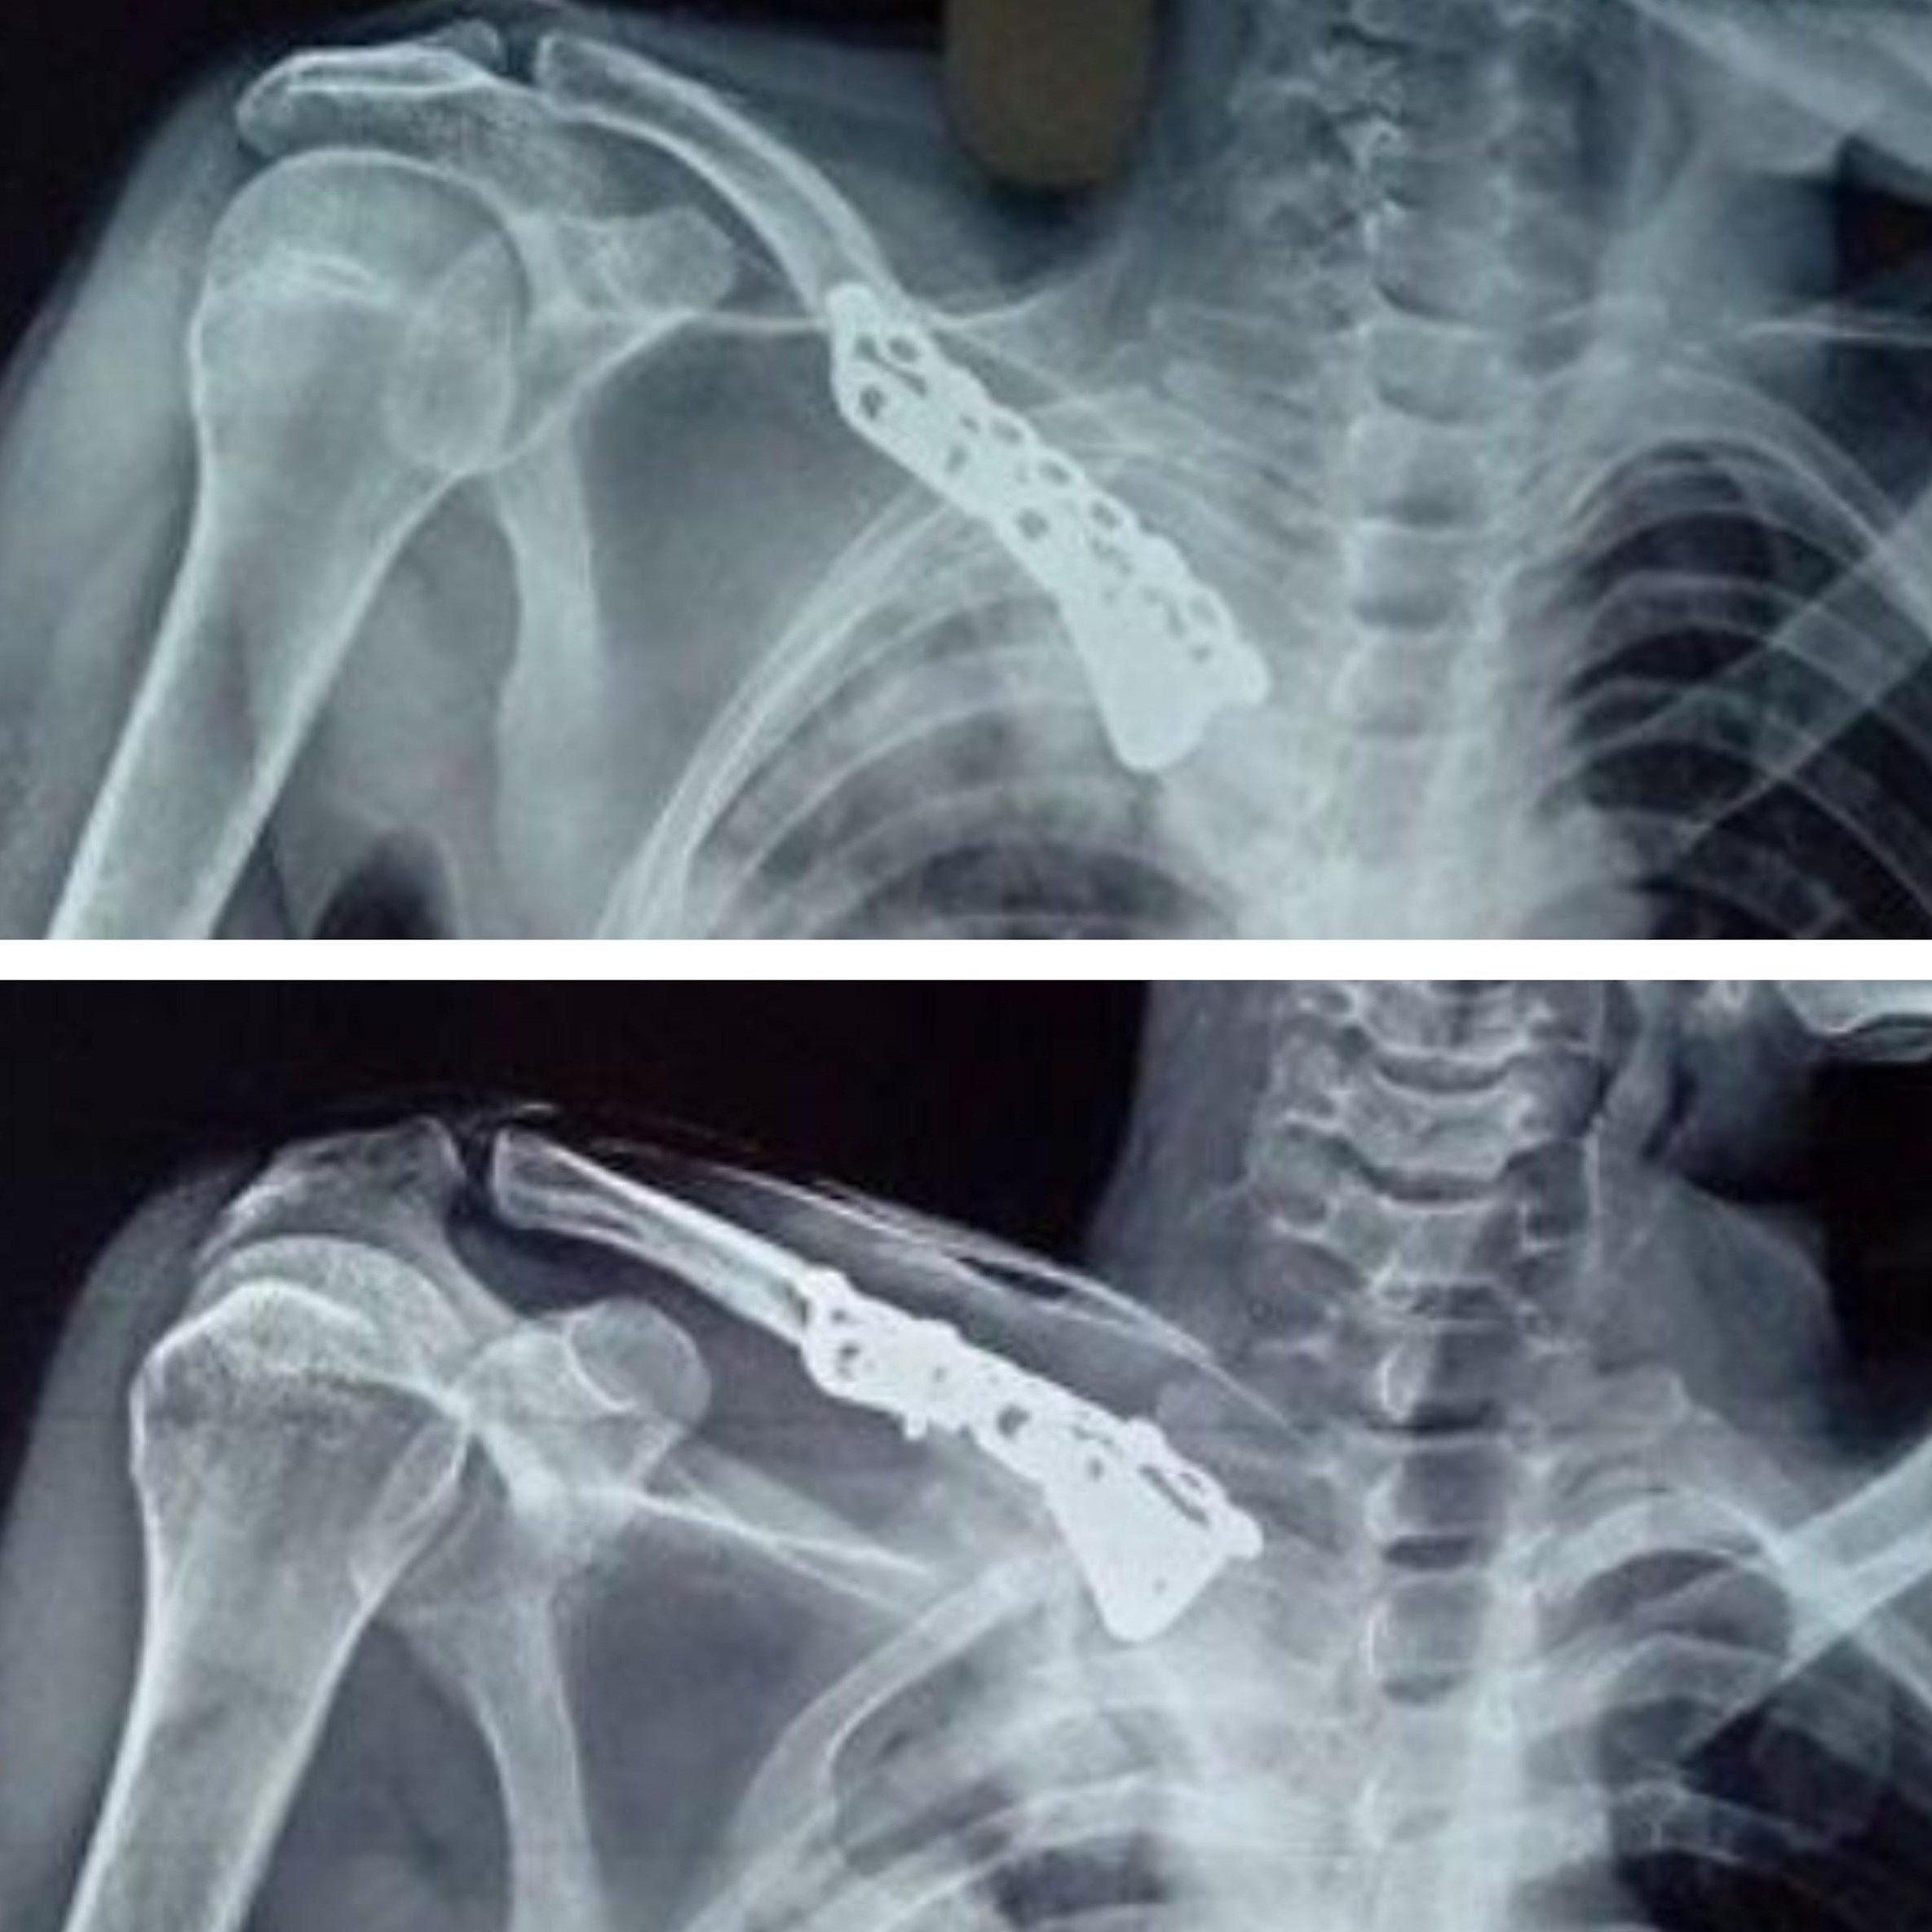

At 12 months follow-up, the X-ray (Fig. 5a and b) showed union with the implant in situ; there was no evidence of implant breakage. At the 12-month functional range of movement, good internal rotation is 80, and external rotation is 90. Abduction ranges from 100 to 110 clinical images (Fig. 6a and b). The pre-operative Constant-Murley score was 34, indicating severe impairment. Post-operatively, this score improved significantly to 85, reflecting good functional recovery. Without any pain, there was hardware prominence. However, the fracture was united, and the function of the shoulder was good, with a good functional range of movement. The patient could return to his previous activity level and perform his daily activities without limitations. The patient was informed about the option of implant removal should the symptoms persist or worsen.

Figure 5: a) Postoperative X-ray at 12 months showing union of the fracture with implants in situ. b) Lateral X-ray confirming union and absence of hardware failure.